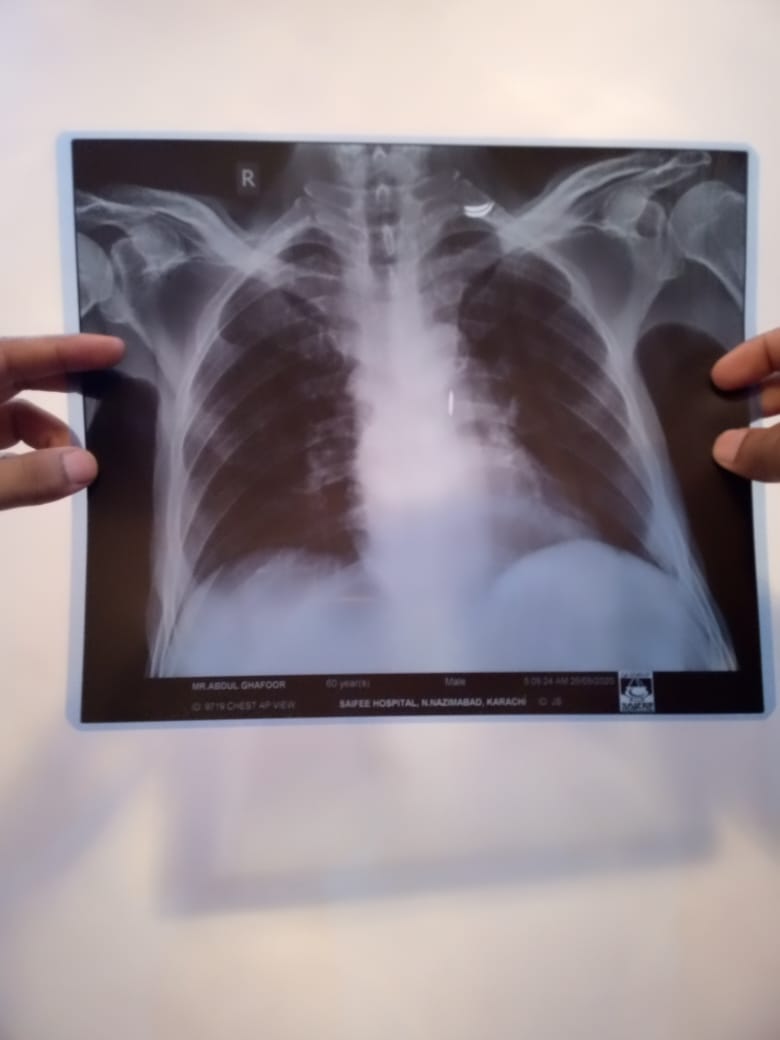

Patient was admitted in hospital due to cancer illness. He didnt have any fever or cough. The doctors performed chest X ray and determined on basis of X ray that patient has contracted coronavirus. I have attached the pictures of the X ray. Please verify if lungs are clear or not.

not necessary that all the patients of cancer have covid 19 but now a days it is nesccery to perform covid test of every immnocompromiz pt. Cancer is one of them . X ray chest is not normal but i m not an xray specialist. All the immunocompromised are nesccery to perform this test and indications to take precautions for doctos . If the test is positive than inform the relatives.